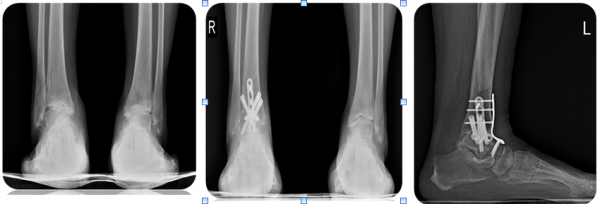

무릎에도 관절염이 있듯이 발목에도 관절염이 있습니다. 하지만 무릎이 퇴행성 관절염인 것과는 달리, 발목은 외상성 관절염이 많다는 차이가있습니다. 물론 발목에도 퇴행성 관절염이나 류머티스 관절염이 흔하게 발생합니다. 그러나, 발목 염좌나 발목 부위 골절의 후유증으로연골손상이 진행되는 경우에는 외상성 관절염이 발생합니다.

SMO 교정 수술 전 후 사진

유합술 수술 전 후, 옆모습 사진

인공관절 치환술 수술 전 후 사진